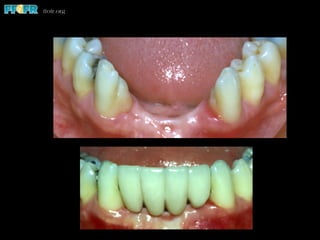

• The mean area of debonded retainers was 38

mm2 compared to retainers that did not debond

(45 mm2)

Thayer, 1993

• Age and gingival position affected the area

available for bonding

Prosthesis failure due

to minimal coverage

More appropriate area

covered

Effect of BondingArea •  The area available for bonding affects success Thayer, 1993 Priest, 1995 Ferrari, 1998 • The mean area of debonded retainers was 38 mm2 compared to retainers that did not debond (45 mm2) Thayer, 1993 • Age and gingival position affected the area available for bonding

• 58.

Prosthesis failure due tominimal coverage More appropriate area covered